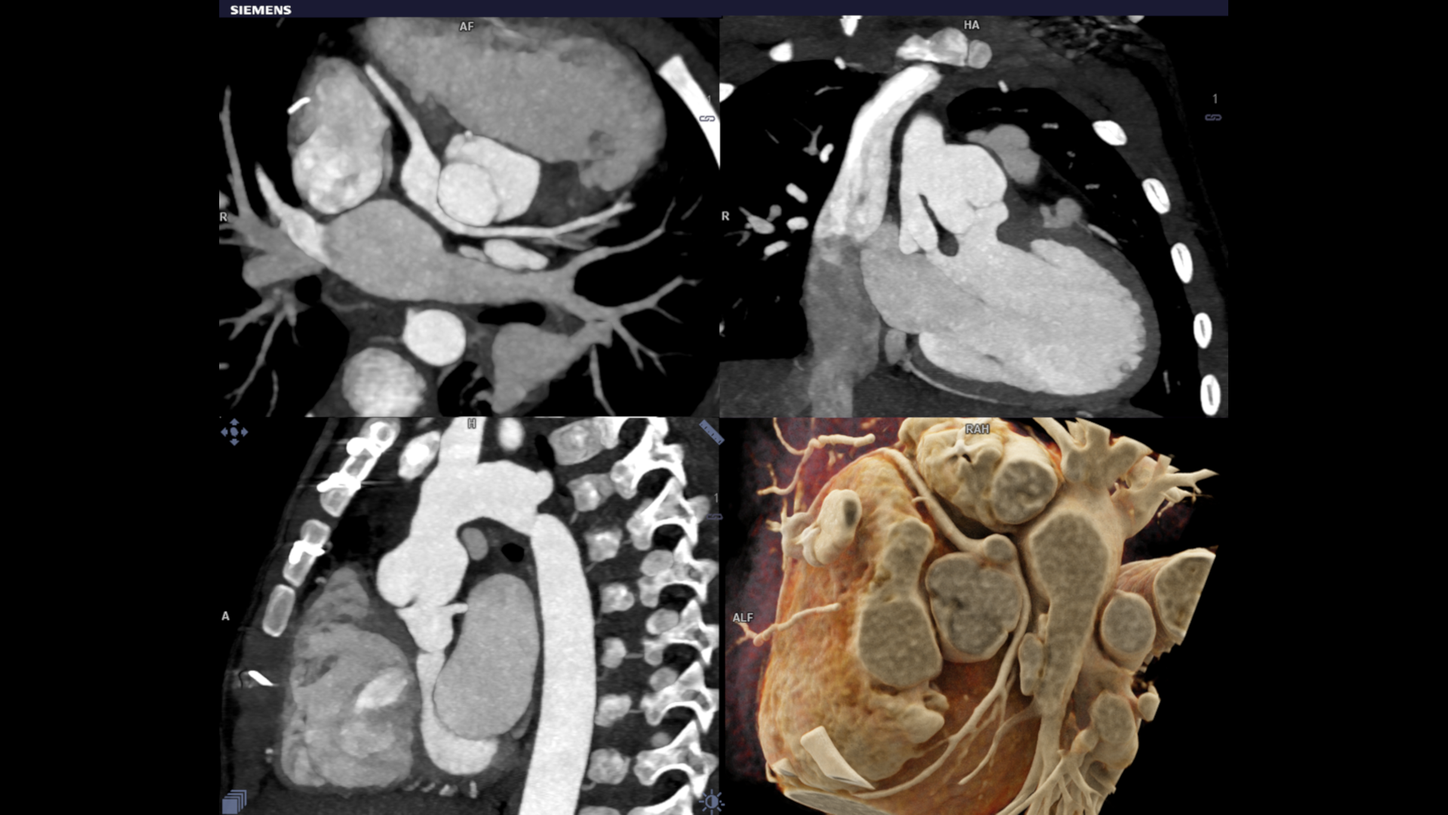

The objective of the whole technique is to get images from the scanning procedure to achieve sound diagnosis in child CHD. Evaluation involving complex anatomy of the body such as the heart, liver, spine & individual blood vessels. The cross sectional details in pediatric imaging are extremely small that demands for good quality imaging. At the same time, radiation dose in this category is a primary concern. Pediatric CT imaging means you have to keep the radiation doses at a bare minimum.

Dual source turbo flash spiral the combination of two sources, a high table feed (increasing scan speed up to 737 mm/s), rapid acquisition (0.25 s) and ultra-fast data transmission, and hence CT scanner makes its high temporal resolution (66 ms ). It enables extremely short scan times with very low radiation doses. Iterative reconstruction technique ADMIRE help to generate high quality images from low dose high noisy data set.

CHD is the most common congenital anomaly and causes more deaths in the first year of life than any other birth defect. Most cases of CHD require surgery or interventional procedures to restore the heart’s normal function. This recent technological improvement has been attributed to better imaging and improved understanding of the anatomy of CHD. Cardiac surgeons and radiologists collaborate in the treatment of children with Congenital Heart Disease (CHD). Faster imaging produces 3D reconstructions and models are to be used as planning tools for surgery. Turbo flash imaging is an excellent choice for the clinical evaluation of CHD especially as the imaging needs to be performed in free breathing and without sedation. Iterative reconstruction technique helps to create quality images from low dose noisy data.